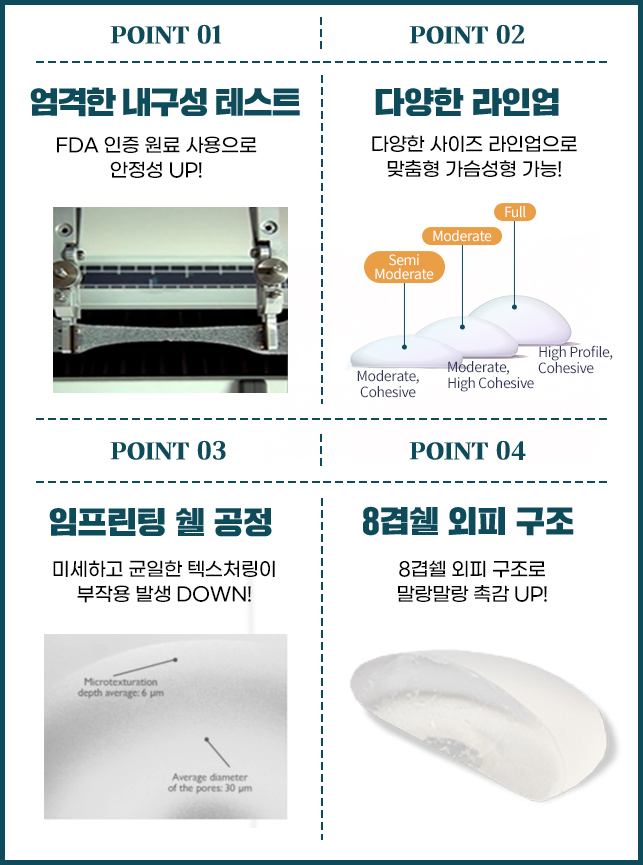

다양한 보형물 라인업

id X SEBBIN Breast Surgery

세빈 엄격한 품질관리